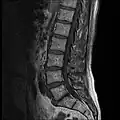

MRI lumbar spine with degeneration (sagittal T1 FSE) -